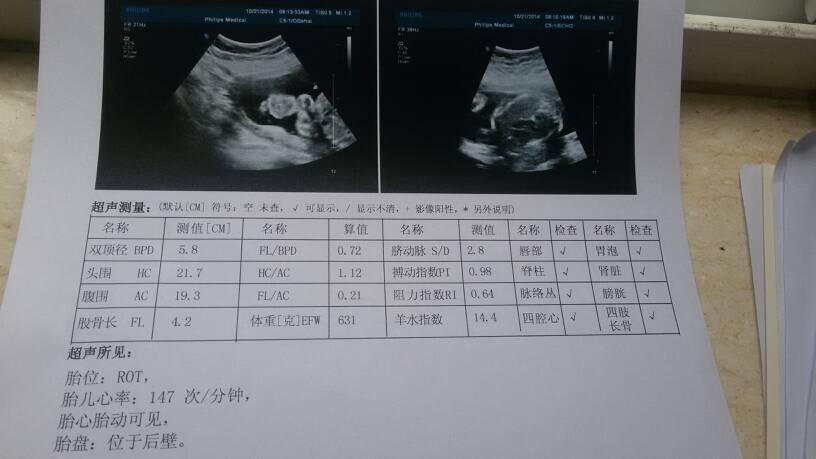

各位宝妈,各位医生麻烦帮我看一下正常么?? 各位宝妈,各位医生麻烦帮我看一下正常么?? 点击展开 么么纳 2014-10-21 09:30 为您推荐: 其他回答 你好,看你的这个检查结果,胎儿大小相当于孕23周,如果你怀孕时间和这个差不多可以不需要担心,其他数据没有问题 一直在路上yw 2014-10-21 21:22 ,,,路过 唯美爱情 2014-10-21 10:19 祝您好孕。 她姓傅 2014-10-21 10:18 非常好啊, 恩典够用 2014-10-21 10:12 我着挺好的 生如夏花般绚烂 2014-10-21 10:01 加载更多 相关问题 麻烦医生宝妈们给看看正常不?宝宝多少天 宝妈们麻烦你们帮我看看这是怎么回事 我就涂了两天的婴儿橄榄油就这样 在线医生麻烦也帮我看下 54天的时候,没胎芽正常吗?请各位宝妈,医生们帮看看